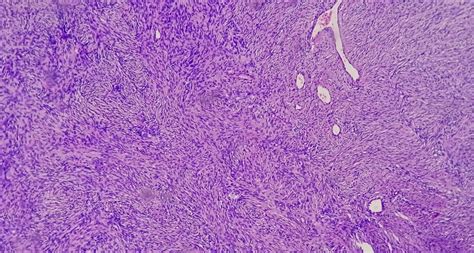

The nerves in our body are insulated by specialized cells known as Schwann cells. When these cells begin to divide uncontrollably, they form a nerve sheath tumor. These growths are broadly categorized based on their cellular origin and their potential to spread. The most common types include schwannomas and neurofibromas. While schwannomas are almost exclusively benign, neurofibromas can occasionally be associated with genetic conditions such as neurofibromatosis type 1 (NF1).